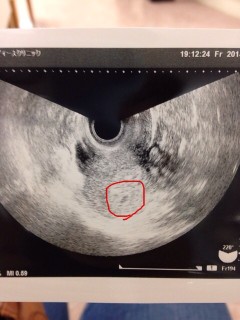

不妊治療を始めて1年と少し。 タイミング療法とHCGで治療してましたが、なかなか授からず、人工授精へステップアップし、最初の人工授精で授かりました!! まだ心拍が確認出来なくて、2週間後にまた受診です。 やっと授かれた赤ちゃん、きちんと心拍うって育ちますように…

初めて受診しました。 胎嚢を確認出来て、「ちゃんと妊娠していますね」と言われました。 すごく嬉しかったです。 胎嚢の大きさは0.84cmでした。 次の受診は2週間後です。 心拍確認出来るといいな!